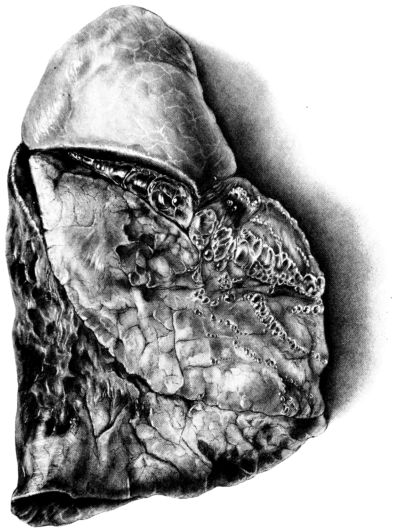

FIG. I. AUTOPSY NO. 99. ACUTE HEMORRHAGIC AND ULCERATIVE LARYNGOTRACHEITIS.

Early in the disease the congestion and the hemorrhages that have been described in the mucous membrane of the nasopharynx (14 and 94) are also conspicuous features in the lining of the trachea and bronchi (Fig. I). This membrane is swollen, turgid, red, and covered by a copious, mucous exudate which may be clear, but much more frequently is blood-stained or opaque and yellowish in color. The blood, variable in amount, may be fresh and red; and after the mucous exudate on the surface is removed, more intense red foci stand out on the congested base (47, 90, 157). Frequently, as the bronchi are approached, the red color of the mucosa becomes more intense and may have a garnet tinge. Membranes such as are encountered in the more usual necrotizing inflammatory processes, like diphtheria, have not occurred in the trachea and larger bronchi in this series (108, 128, 157).[3] The exudate peels off readily, and as indicated above, leaves a velvety red surface, 14dotted here and there with darker or more intensely red foci. Small ulcerations of the mucosa occur, but are inconspicuous (82, 156). As the finer ramifications of the bronchi are approached, the accumulation of the exudate in their lumina becomes more and more marked, and on cross section of the lung, they often stand out conspicuously on account of their increased size and projecting, seromucous, blood-stained content (101, 149, 162).